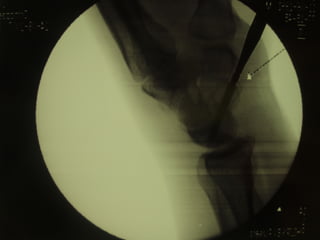

Radiography

 The 4 essential views (ie, PA, lateral, supinated and

pronated obliques) identify majority of fractures.

 The scaphoid view is a PA radiograph with the wrist

extended 30° and deviated ulnarly 20°. This view

helps to stretch out the scaphoid and is also used for

assessing the degree of scaphoid fracture angulation.

 A clenched-fist radiograph has also been useful for

visualization of the scaphoid waist.

Radiography  The 4essential views (ie, PA, lateral, supinated and pronated obliques) identify majority of fractures.  The scaphoid view is a PA radiograph with the wrist extended 30° and deviated ulnarly 20°. This view helps to stretch out the scaphoid and is also used for assessing the degree of scaphoid fracture angulation.  A clenched-fist radiograph has also been useful for visualization of the scaphoid waist.